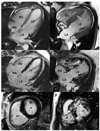

Cardiac morphology is normal in preclinical HCM, even with the use of gadolinium-contrast cardiac MRI (Gd-CMR). Below are images from 2 subjects with a myosin heavy chain missense mutation. As illustrated, sarcomere mutation carriers without LVH do not typically demonstrate late gadolinium enhancement (LGE), indicating that gross myocardial scar is not a prominent feature of the preclinical stage. In contrast, the majority of patients with overt HCM have demonstrable LGE.

1. A, C, E- Preclinical HCM: Gd-CMR revealed no morphological abnormalities suggestive of HCM. Note the absence of LVH or late gadolinium enhancement VSports注册入口.

2. B, D, F- Overt HCM: Gd-CMR demonstrated typical findings of HCM, including a markedly thickened septum (panel B; arrow) associated with areas of heterogeneous epicardial LGE, affecting over 50% of total LV mass and involving the anteroseptum (panel D; arrow) and the inferoseptum (panels D and F; arrows).

RV=right ventricle; LV= left ventricle; RA=left atrium; LA=left atrium; LGE= late gadolinium enhancement.